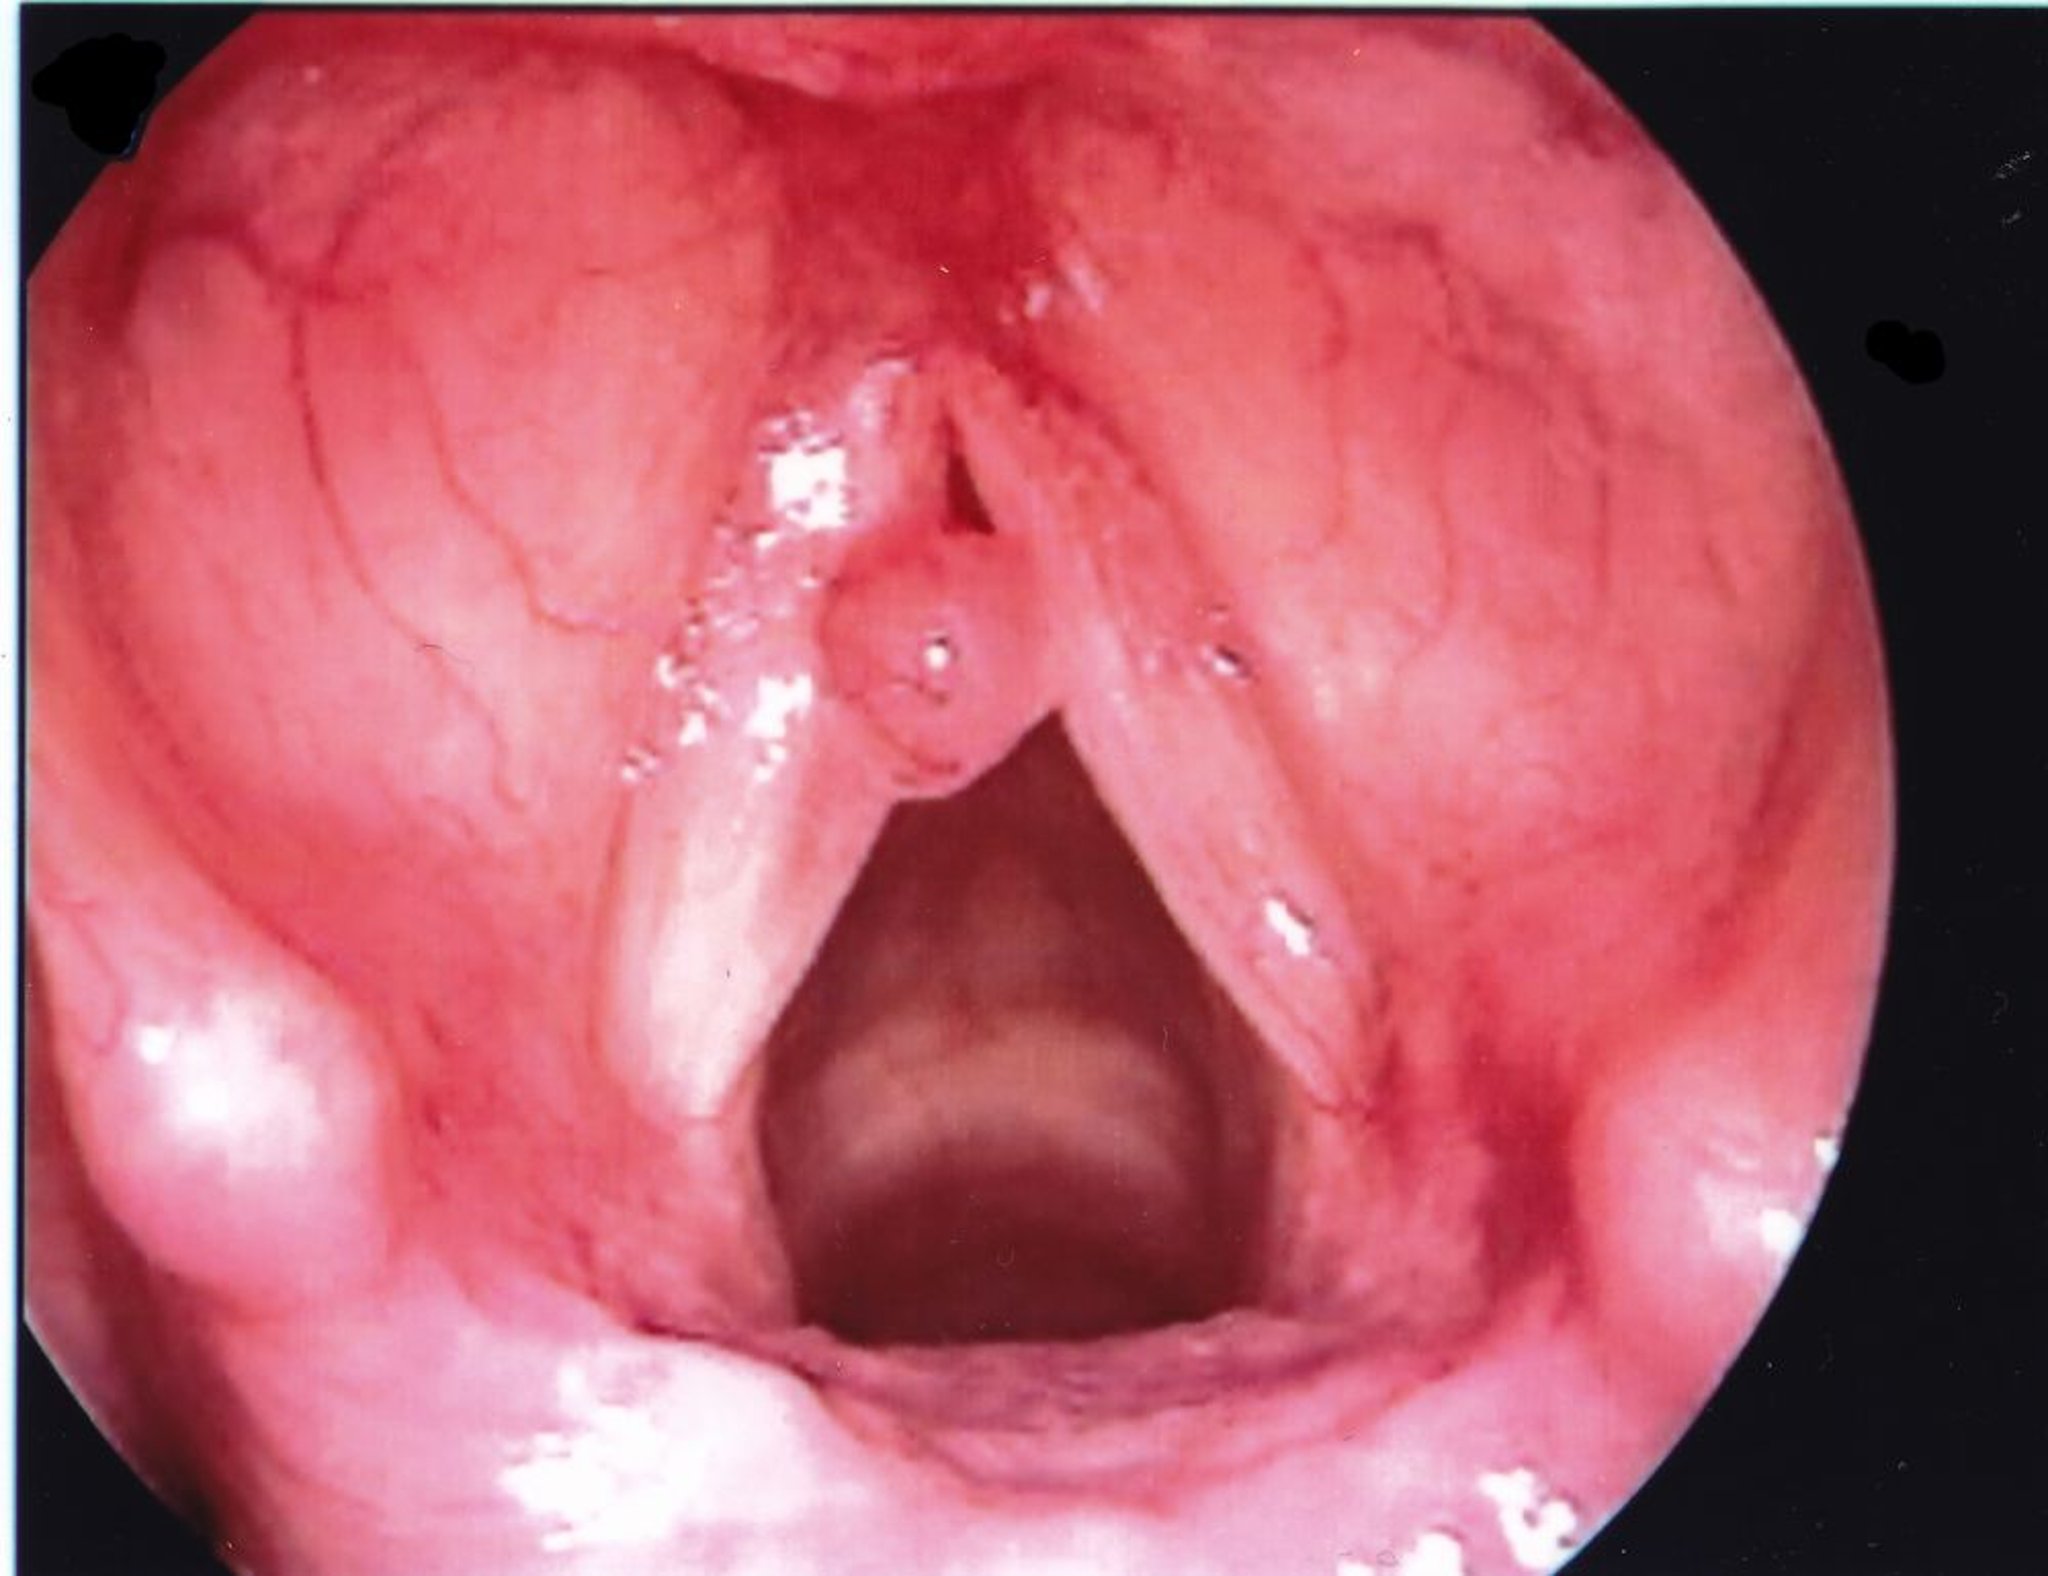

Pólipo de las cuerdas vocales

Un pólipo en la cuerda vocal suele manifestarse unilateralmente y más grande que un nódulo.

Imagen proporcionada por Eiji Yanagisawa, MD.